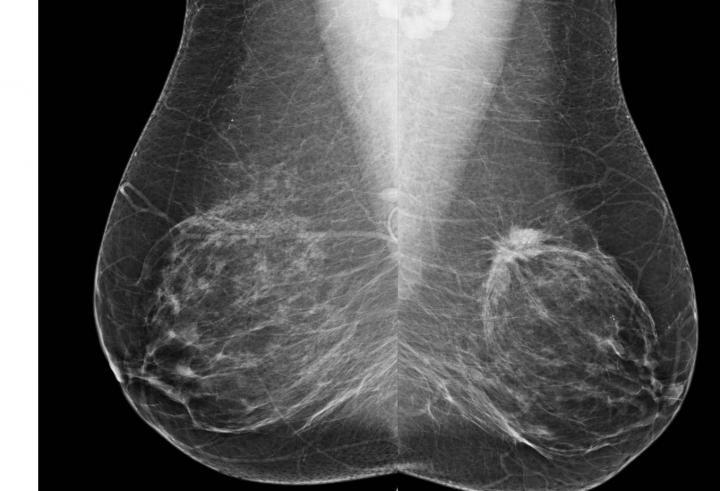

These are bilateral MLO views from screening mammography.

(Photo Credit: RSNA)